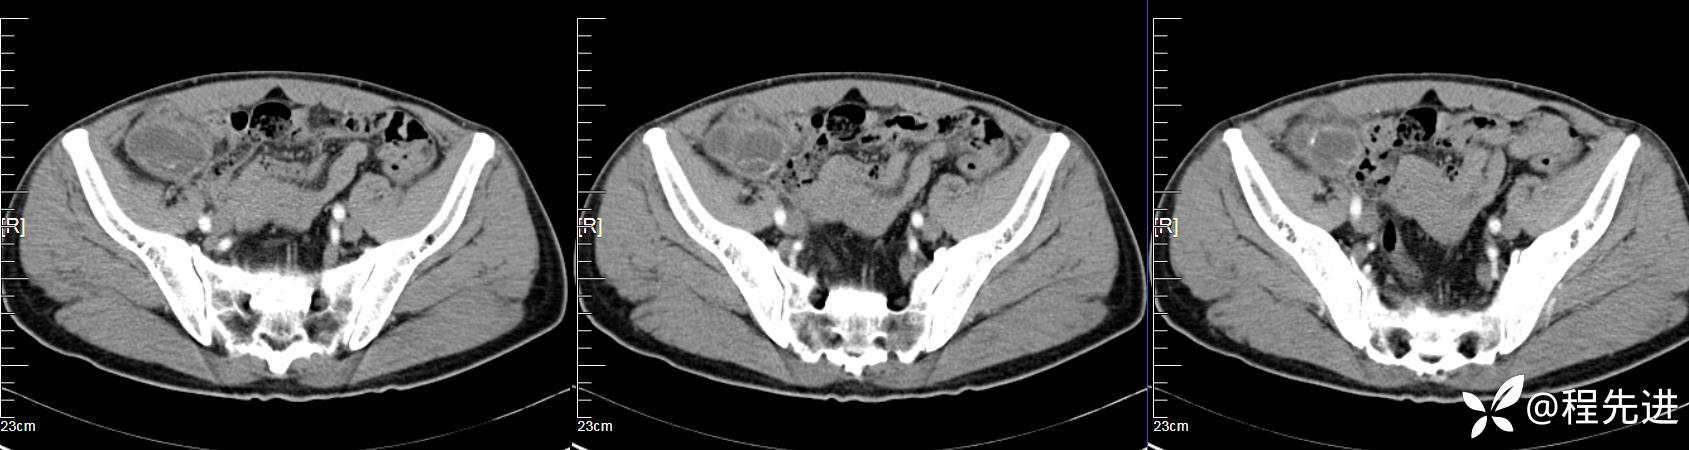

【患者信息】:男,61岁

【现病史及既往史】:右下腹部疼痛伴腹胀2天

【影像检查】